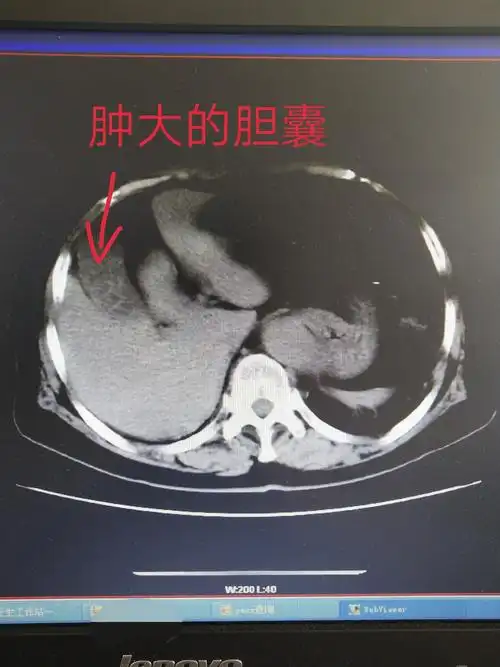

腹部ct提示:胆囊结石胆囊炎,右肾多发结石.